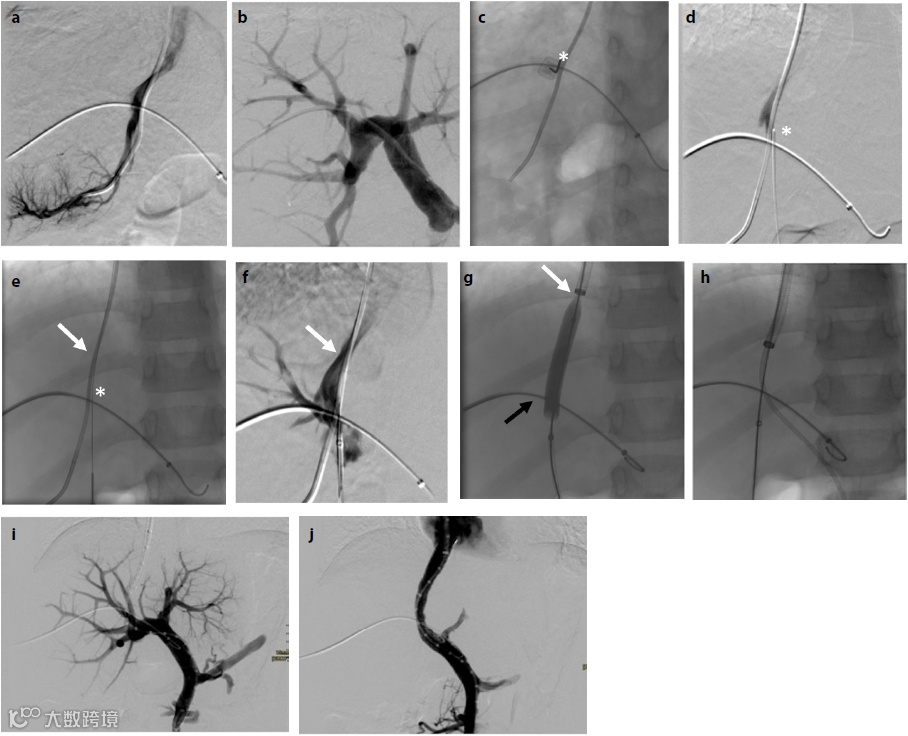

门静脉高压(PHT)及其后遗症是囊性纤维化相关肝病(CFLD)最重要的临床表现。近日,来自比利时根特大学的Hermie L等人评估了预防性经颈静脉肝内门系统分流术(TIPS)在预防儿童CFLD患者PHT相关并发症中的安全性和有效性,相关内容发表在Diagn Interv Radiol杂志上。

该项前瞻性单臂研究纳入了2007年至2012年间在单个三级囊性纤维化中心接受预防性TIPS治疗的伴有CFLD、PHT体征和肝功能保留的儿童患者,并评估该方法的长期安全性和临床疗效。

结果显示,研究者对7名平均年龄9.2岁(±标准差:2.2)的患者进行了预防性的TIPS。所有患者都成功完成了手术,预估中位通畅期为10.7年[四分位数范围(IQR):0.5~10.7]。中位随访9年(IQR:8.1~12.9),未见静脉曲张出血。在两名患有晚期PHT和快速进展期肝病的患者中,严重的血小板减少症无法停止。随后的肝移植发现两例患者均为胆汁性肝硬化。其余早期PHT和较轻的门窦血管病患者未出现症状性脾功能亢进,肝功能在随访结束前保持稳定。2013年,在一次严重肝性脑病发作后,纳入行为。

因此,在部分囊性纤维化相关PHT患儿中,TIPS是一种可行的治疗方法,可长期保持通畅,避免静脉曲张出血。然而,由于不可避免的肝纤维化、血小板减少和脾肿大进展,预先放置的临床益处似乎很小。

简评丨袁敏

TIPS治疗门静脉高压及其并发症在成人患者中已经广泛运用,但应用于儿童尚无相关指南或共识参考,加之儿童生长发育带来的不确定性以及儿童门静脉高压的病因和疾病谱与成人有很大差异,因而TIPS治疗儿童门静脉高压的研究和报道远远少于成人。本研究为前瞻性、单臂研究,优先TIPS预防性地用于儿童囊性纤维化相关肝病(CFLD)导致的门静脉高压及其并发症(但这些患儿并未发生出血等不良事件),中位随访时间长达9年,探讨其长期的安全性和有效性,认为在此类患儿中TIPS在技术上是可行的,具有良好的支架长期通畅率,手术可以预防和避免静脉曲张出血等门静脉高压不良事件的发生,但是TIPS并不能阻止或延缓患儿的肝纤维化、脾大、脾亢、血小板减少的进展,因此预防性TIPS对此类患儿的实际临床获益有限。

不足之处:①TIPS用于未发生出血、腹水等门静脉高压不良事件的非肝硬化门静脉高压患者是存在争议的,本试验仅仅是一项严格控制条件的、经伦理审核通过的前瞻性、小样本探索性研究;②入组患儿中只有2例为PPG达到17 mmHg的显著性门静脉高压,5例PPG仅为6~10 mmHg的早期门静脉高压,不具有代表性;③样本量小,且没有设常规治疗作为对照组,普遍性意义较小,当然可能和CFLD发病率较低,没有足够的患者基数有关。